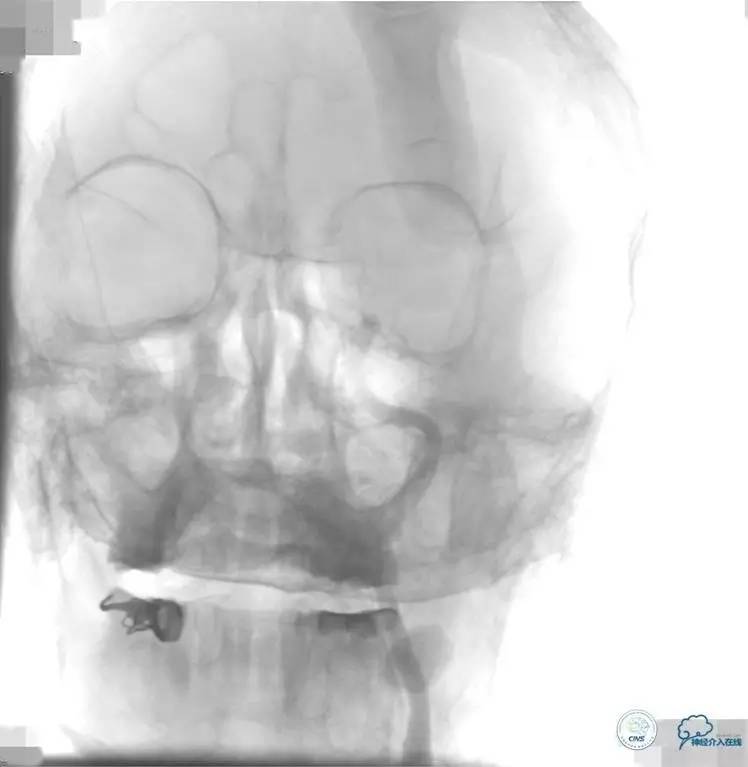

2015-06-05脑血管造影:左侧颈内动脉闭塞。

评估患者侧支循环,考虑患者发病时间超过6个多小时,未行血管内治疗。